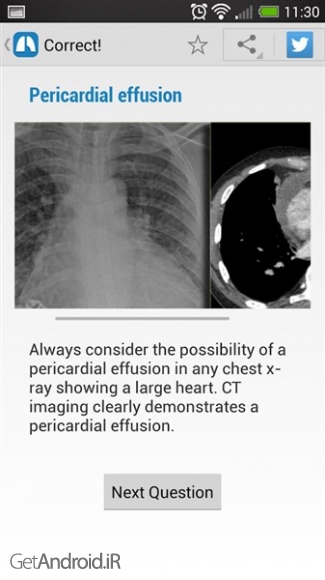

- حل بیش از 100 مورد بالینی

- تحت پوشش داشتن بسیاری از موارد همچون ریه نادر، قلب، استخوان، بافت نرم، وغیره

- وجود بیش از 380 تصویر با كیفیت بالا

این یك منبع ضروری و سودمند برای شما میباشد.مناسب برای USMLE, FRCR, MRCP و اصلاح نهایی پزشكی